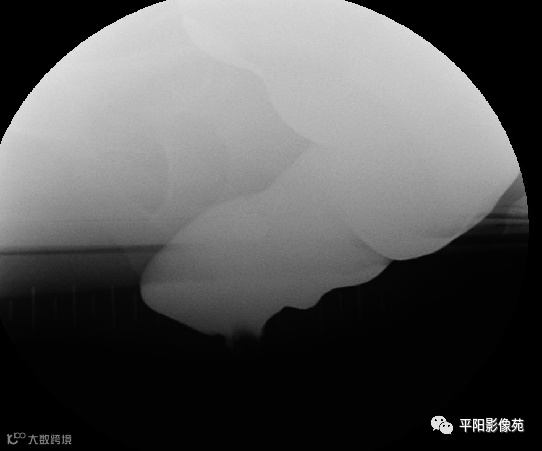

排粪造影

直肠壁部分或全层向下移位,称为直肠脱垂(rectal prolapse)

直肠壁部分下移,即直肠黏膜下移,称黏膜脱垂或不完全脱垂

直肠壁全层下移称完全脱垂

排便造影钡(x射线)排便造影或排便直肠造影是诊断排便障碍的公认临床

钡排粪造影实时评估直肠壁形态、盆底运动和排空。